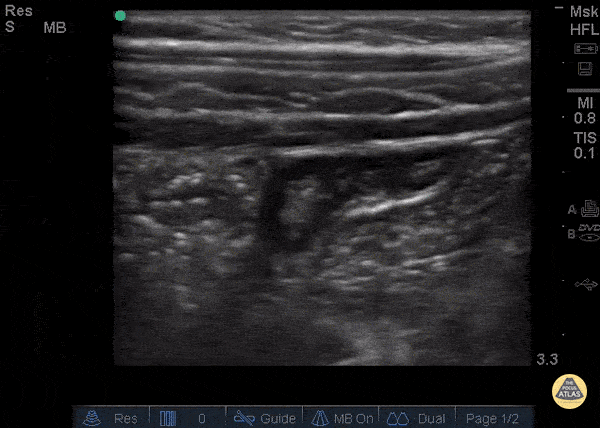

Bowel-GI - Normal Appendix - Blind End

A normal appendix is identified by a blind-ending tubular structure (as seen in this image). It should be <6mm diameter measured from outer wall to outer wall (although 6mm-7mm has also been described). This patient’s appendix was measure to be 5.4mm (see still image). Dr. Sathya Subramaniam - Children’s Hospital of Philadelphia